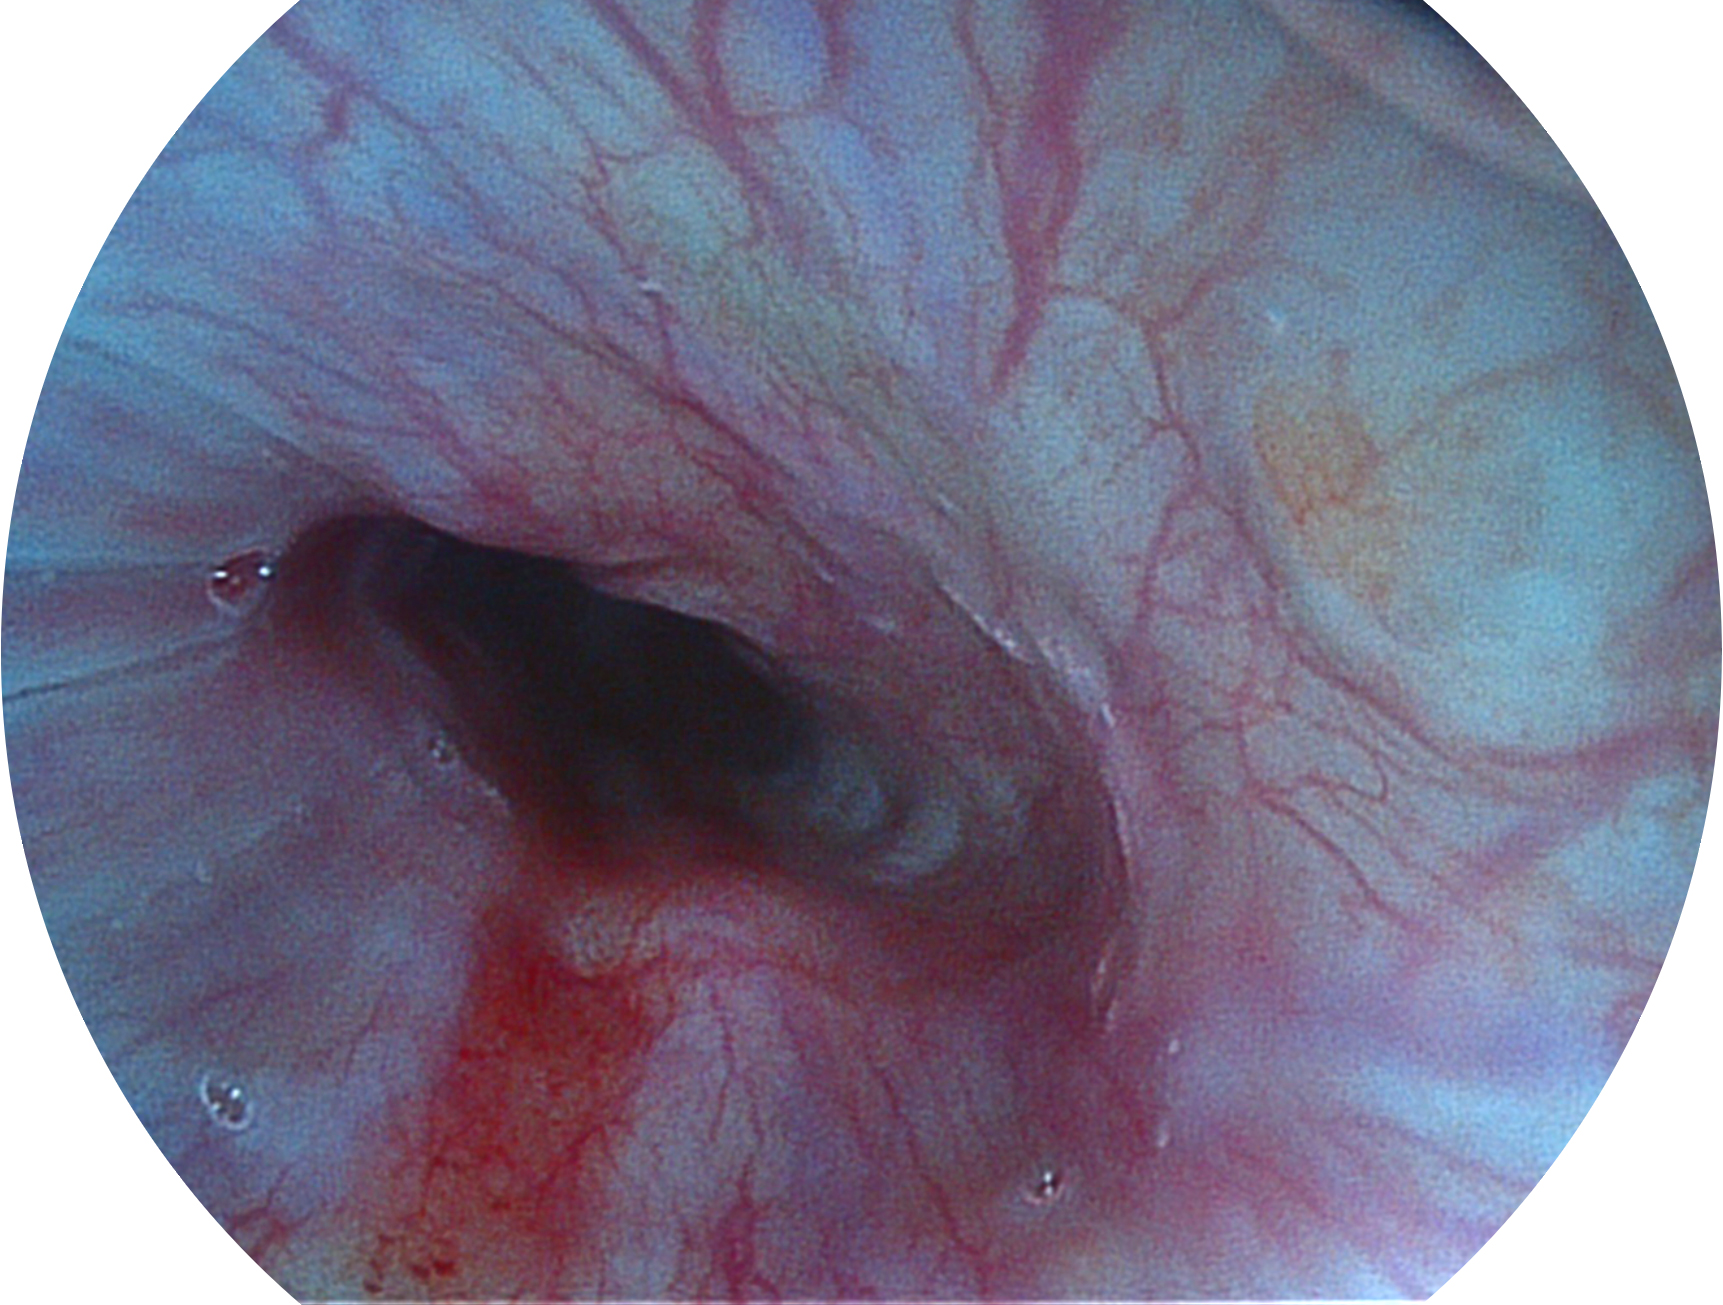

16877太阳集团新开发的内镜染色技术,主要是基于多波长LED 光源的开发,VLS-55Q 四波长LED 光源是由四个不同颜色的LED光按照相应照明模式所规定的特定发光比例进行合束后形成,合束后形成的照明光的光谱由红光、绿光、蓝光及蓝紫光这四个不同的波段范围构成。具有更高光谱自由度,通过光谱比例的控制,实现了聚谱成像技术,英文全称为“Spectral Focused Imaging, SFI”,缩写为“SFI”和光电复合染色成像技术,英文全称为“Versatile Intelligent Staining Technology, VIST”,缩写为“VIST”。